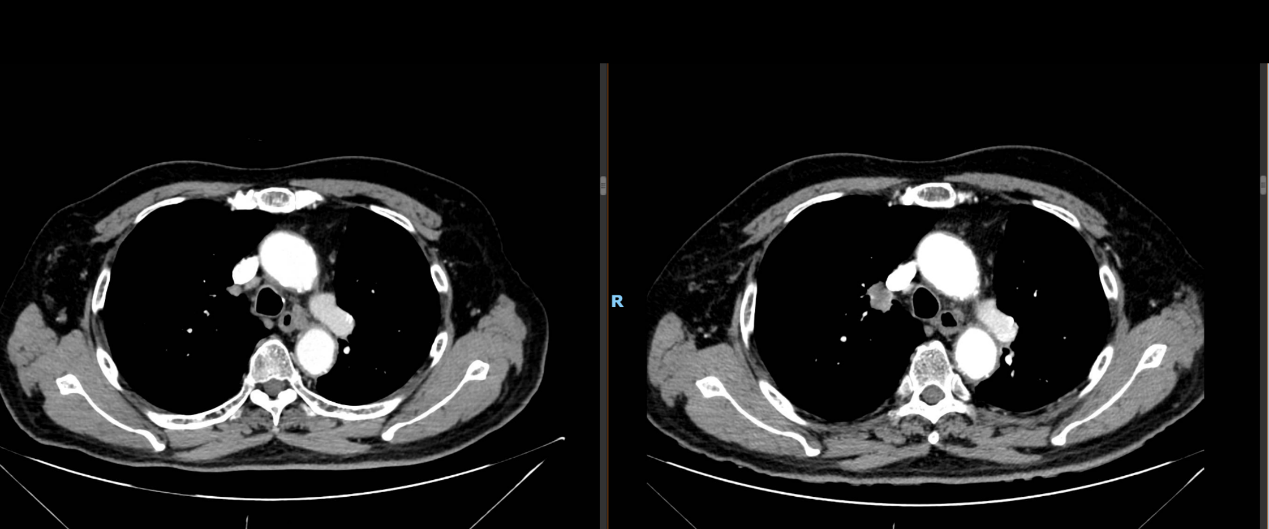

MDT:胸外科会诊考虑有手术机会,患者肺功能不佳(见图4),风险较大,患者拒绝。